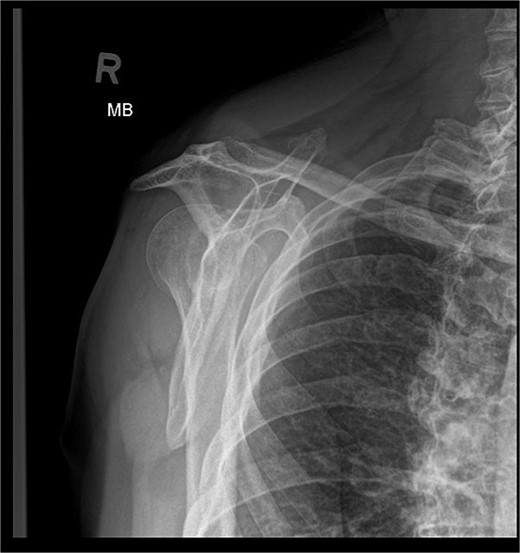

Patient is a 67-year-old male who participated in a road accident on 28 April 2020. As a result of the accident, the motorcycle driver suffered a direct injury to his right shoulder. Immediately after this event, the patient was transported, diagnosed, and treated in the Emergency Ward, where shoulder contusion was diagnosed.

X-ray images can be found in Figs 1 and 2.

After the diagnosis at EW, the decision was made to pursue with the conservative treatment.

During the outpatient follow-up visit at the Orthopedic Clinic, ~10 weeks after the accident, a physical examination of the patient was conducted, which included shoulder X-ray imaging. The examination revealed severe pain in the right shoulder and a significant limitation in the mobility of the joint (results summarized in Table 1). The above enforced the decision of expanding the imaging diagnostics to look for fractures within the humeral head; hence, computed tomography (CT) and magnetic resonance imaging (MRI) examinations of the right shoulder were carried out. Additional imaging studies revealed a depression fracture of the humeral head covering 2/3 of the articular surface with posterior subluxation of the right shoulder joint. The examination also revealed that the continuity of the tendons of the rotator cuff muscles has been preserved.